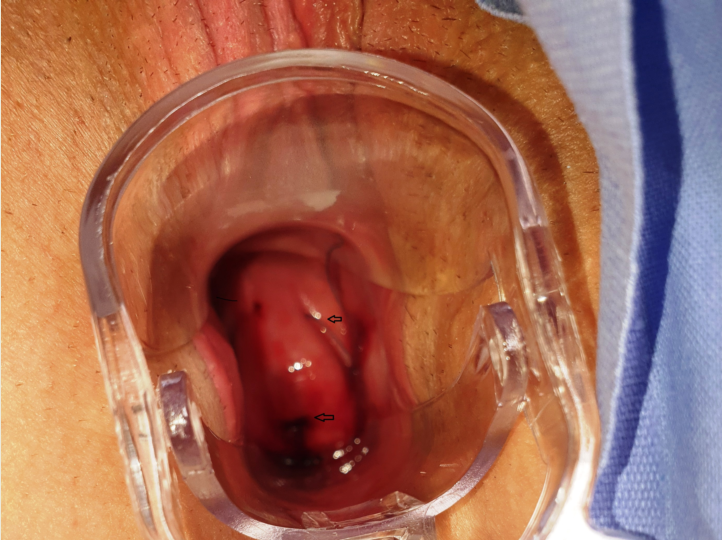

Abstract Purpose Since their introduction, intrauterine devices (IUDs) have been associated with various complications. Avery rare complication is the perforation of the cervix by the strings of the IUD. Purpose of the current study is to present a novel case of cervical perforation by the strings of a copper IUD and to perform a systematic review of the literature. Materials and Methods The patient a 43-year-old attended the gynecology clinic in order to remove her copper IUD. Speculum examination revealed that both the strings of the IUD perforated the anterior lip of the cervix. Management options were offered, the patient opted for a hysteroscopic removal. We searched the electronic databases: MEDLINE, Cochrane Library,Google Scholar,EBSCO for similar cases. Results Electronic search yielded 1821 articles; 8 were selected for inclusion. Mean age of the women was 35,37±7,781, range (26-47) years. One woman (12.5%) was nulligravida;3 women were multigravida (37,5%). Seven women (87,5%) were asymptomatic. Three IUDs (37,5%) were LNG-IUS; 5 IUDs (62,5%) contained copper. Conclusions Cervical perforation by the strings of IUD is an extremely rare clinical entity. It is asymptomatic in general and in most cases the strings of the IUD may be returned back to the endocervical canal after surgical maneuvers.